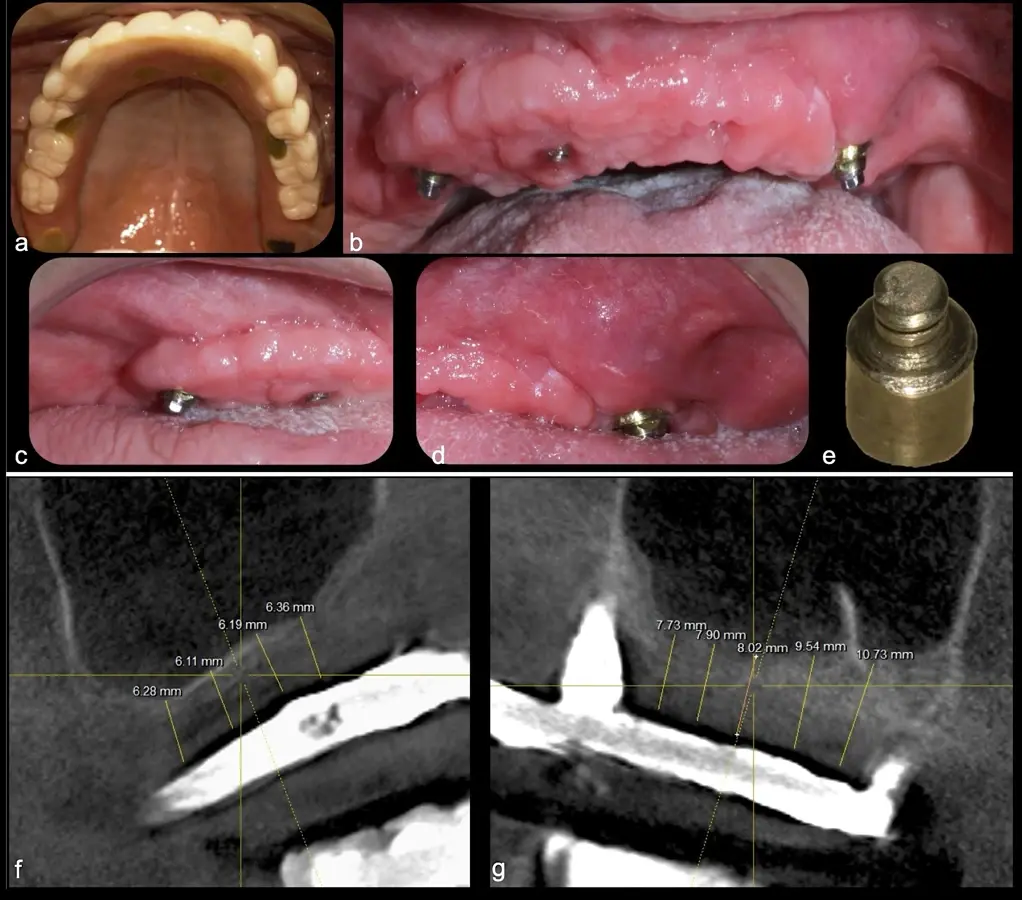

El levantamiento de piso de seno maxilar es una técnica quirúrgica aceptada previa o simultáneamente a la colocación de implantes dentales. La mayor evidencia científica refiere que si se tiene entre 0 -7 mm de altura ósea se debe realizar la elevación sinusal junto con injertos óseos; y a partir de los 8 mm, se hace más predecible la colocación simultánea de implantes dentales.1-3

Aunque esta técnica es predecible, la perforación de la membrana sinusal es la complicación intraoperatoria más común, con una prevalencia de hasta el 58.3%.4 Existen también otras complicaciones reportadas, como hemorragias asociadas a la lesión de la anastomosis arterial en el área de la pared lateral del seno maxilar.5-8

La técnica se inicia con la colocación de anestesia infiltrativa, posteriormente se realiza una incisión crestal o paracrestal con posibles liberantes verticales que deben de estar alejadas por lo menos 5 mm de los límites de la futura ventana y sobrepasar la línea mucogingival. Se realiza una elevación de colgajo, se inicia la antrostomía y antroplastía. Para ello, se emplea el inserto redondo diamantado de corte al momento de delimitar los bordes de la ventana de acceso. Luego se cambia al inserto aserrado liso de calibre fino con superficie diamantada, para profundizar y eliminar el hueso en el contorno de la ventana. Una vez que se traslucen los tejidos, se puede optar por el retiro de la tapa ósea o el levantamiento de ésta junto con la membrana.

Se inicia la elevación de la membrana de Schneider con el inserto redondeado no cortante en forma de disco, empleando movimientos suaves. El levantamiento puede complementarse con elevadores convencionales, siguiendo la dirección mesiodistal. La fase de desprendimiento inicia con el piso y sigue hacia la pared mesial para terminar, y de ser necesario, hacia la pared posterior. Existen diversos insertos con angulaciones y longitudes para mayor accesibilidad16 (Figura 1).

El tipo de inserto a ser utilizado dependerá del espesor de la pared ósea. Si la pared es menor a 0.5 mm, es mejor utilizar insertos de desgaste para prevenir la ruptura de la membrana de Schneider; si el espesor es mayor a 0.5 mm, se puede utilizar insertos de corte de espesor medio (Figura 3).

El clínico puede retirar la tabla ósea o introducirla como “tienda de campaña” dentro del seno maxilar. En cualquiera de las alternativas, es importante evaluar la presencia de tabiques óseos y de la arteria postero alveolar superior.